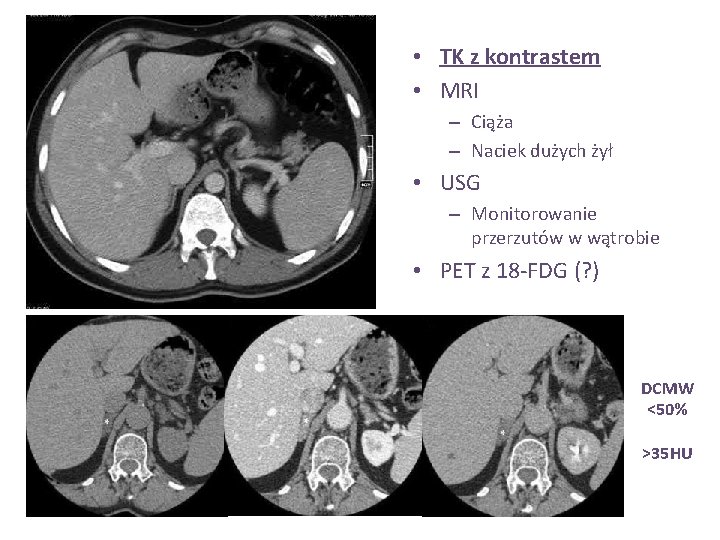

• TK z kontrastem • MRI – Ciąża – Naciek dużych żył • USG – Monitorowanie przerzutów w wątrobie • PET z 18 -FDG (? ) DCMW <50% >35 HU